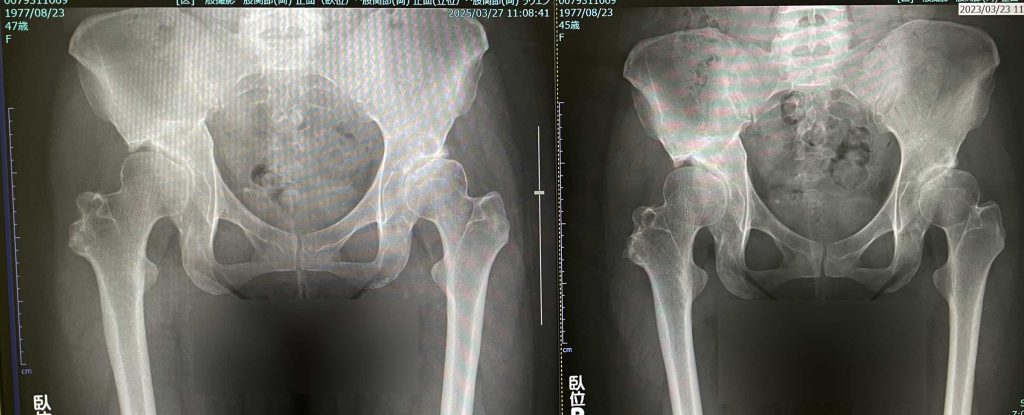

今回のレントゲン

2年前との比較。

左股関節3年比較

・2年前と比較してそんなに大きく変わっている様子はない。多少隙間が狭くなった感じはある